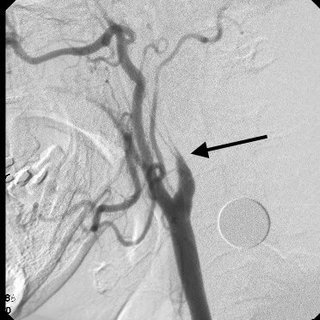

If cervical dissection is suspected, many diagnostic modalities may confirm the diagnosis. The initial and least invasive screening tool is a carotid ultrasound; its sensitivity is not as good as CT angiogram and it does not allow for imaging of the intracranial vessels. A CT angiogram is more commonly ordered these days as it can be done concurrently with a brain CT looking for acute stroke or intracranial bleed.

A flame sign is a classical sign that can be seen; it is due to tapering of the carotid artery. MRI and MRA are reasonable alternatives to CT if the patient has contraindications to CT angiogram.

According to ESO guidelines, a carotid artery dissection should be split into extracranial artery dissection (EDA) and intracranial artery dissection (IAD). EAD refers to the dissection of a cervical carotid or vertebral artery radiologically confirmed by the presence of a mural haematoma, a dissecting aneurysm, a long tapering stenosis, an intimal flap, a double lumen or an occlusion >2 cm above the carotid bifurcation revealing a dissecting aneurysm and/or a long tapering stenosis after recanalization.